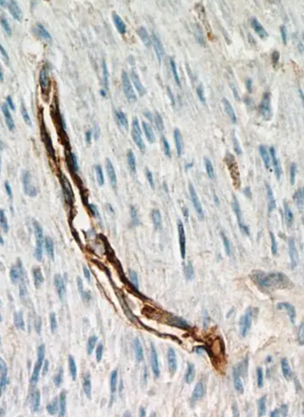

CD34+ 干细胞是一类重要的多能祖细胞,主要存在于骨髓、外周血和脐带血中,具有自我更新和分化为多种细胞类型的潜力。它们在造血系统、血管生成和组织修复中发挥关键作用,并可能参与肝脏、心脏等器官的再生。

CD34 是一种细胞表面糖蛋白,属于唾液黏蛋白家族,参与细胞间黏附、迁移和信号传导,主要表达于造血干细胞/祖细胞(HSPCs) 、血管内皮祖细胞(EPCs)和某些间充质干细胞(MSCs)亚群,可来源于不同组织。

CD34+ 干细胞具有多谱系分化能力,可生成多种细胞类型,包含造血分化系统和非造血分化系统(争议性)。前者可进一步分化为髓系细胞(粒细胞、单核细胞、巨噬细胞)、淋巴系细胞(T细胞、B细胞、NK细胞)和红细胞及血小板;后者是近年研究发现,CD34+ 细胞在特定条件下可能分化为肝细胞样细胞(HLCs)、血管内皮细胞、心肌样细胞和神经样细胞,但非造血分化效率较低,且机制尚不明确,需进一步验证。目前,CD34+干细胞常应用于造血干细胞移植、血管再生治疗、肝脏再生研究和组织工程与再生医学等方面,其分离方法通常为免疫磁珠分选(MACS)和流式细胞分选(FACS)两种,其中免疫磁珠分选为常用的分离方法。